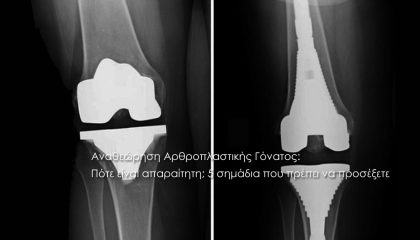

Read more + 15 Φεβρουαρίου, 2026 By Roidisnt in Post

Read more + 13 Φεβρουαρίου, 2026 By Roidisnt in Post

Read more + 1 Φεβρουαρίου, 2026 By Roidisnt in Post

Read more + 18 Ιανουαρίου, 2026 By Roidisnt in Post

Read more + 2 Νοεμβρίου, 2025 By Roidisnt in Post

Read more + 15 Οκτωβρίου, 2025 By Roidisnt in Post